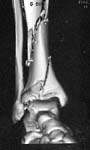

Please see images (shrunk as much as practical) below of a 22 year old man sent on to me 2 weeks after a climbing accident. Initial treatment in a plaster.

Treated by us with "minimal" internal fixation and application of a hybrid frame with 2 rings and wires around the metaphysis and 3 half pins in the diaphysis. Stable construct achieved. Tibial articular surface is well reconstructed-the lateral views are not included but show no articular steps or irregularity and the talus is well centred in the sagital plane.

Question is regarding the talus which had a lateral corner fracture as can be seen. This was a crush and was ungraftable. Now we can see some talar tilt and presumably this constitutes a risk factor for early OA. Are there any measures we could take? Ankle distraction? Limited weight-bearing for how long ? Other measures?